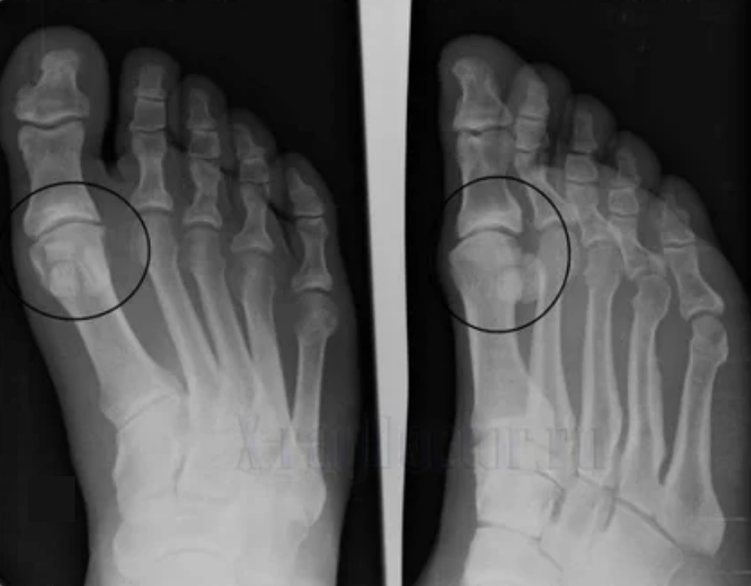

Om een diagnose te stellen, bestuderen reumatologen de klachten van de patiënt en schrijven ze een X -Ray -onderzoek voor. Meestal wordt radiografie gebruikt in 2 projecties. De arts kijkt naar de aanwezigheid van dystrofische aandoeningen in hyalinekraakbeen en botgewrichten. Als de articulaire opening wordt verminderd, de botten vervormd of afgeplat worden, zijn er cystische formaties op het oppervlak van het kraakbeen, osteofyten zijn duidelijke tekenen van artrose. Tijdens de inspectie geeft artrose de instabiliteit van het gewricht aan: de as van de ledematen en subluxatie is verstoord.

Vaak kan een X -Ray -afbeelding geen volledige informatie geven over de toestand van het gewricht. Voor een grondiger onderzoek wordt computertomografie voorgeschreven, het is effectief voor het onderzoeken van botten. MRI wordt vaker gebruikt om zachte weefsels te bestuderen.